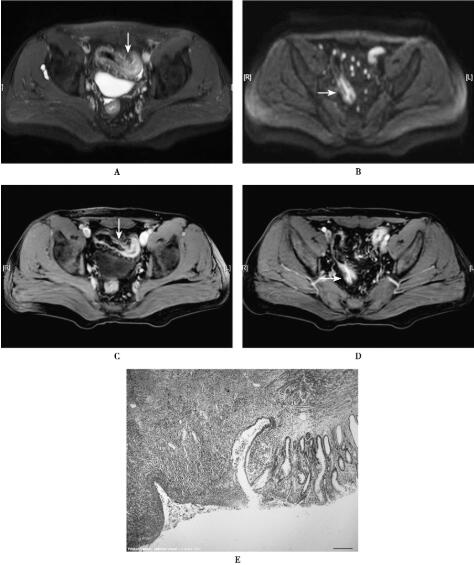

图1溃疡性结肠炎

MRI平扫SPAIR(A)乙状结肠肠壁不均匀增厚,边缘毛糙,DWI(B)呈高信号,增强扫描(C-D)呈不均匀强化。病理(×40倍)光镜(E)观察病变位于粘膜及粘膜下层,粘膜固有层炎症细胞数目增加,隐窝脓肿(即腺腔内中性粒细胞聚集)出现,裂隙样结构形成。间质内大量中性粒细胞、淋巴细胞、浆细胞、嗜酸性粒细胞浸润,腺体结构被破坏